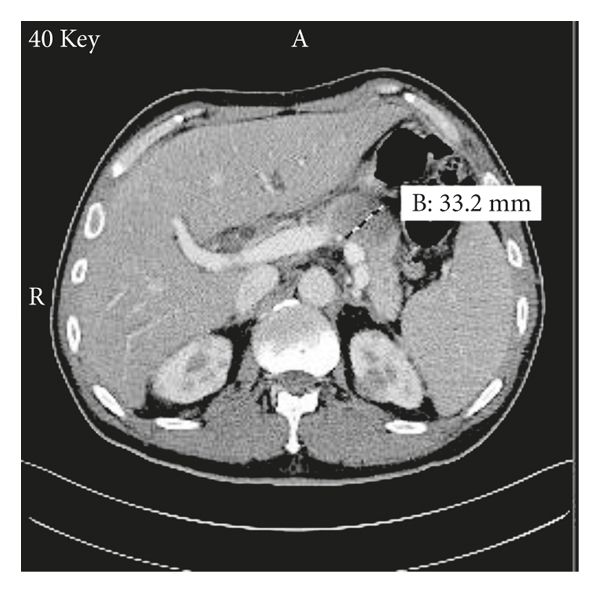

A 48-year-old man with no significant past medical history presents to the emergency department with 1 week history of worsening jaundice associated with passage of dark coloured urine and pale stools. He denied abdominal pain, fever, chills, rigors, or night sweats. He had no skin rashes, pruritus, or easy bruising. He also reported no anorexia or unintentional weight loss. He was a nonsmoker and a nonalcoholic with no family history of malignancy. Vital signs were normal and physical examination was positive only for generalized icterus. He had no peripheral lymphadenopathy. Complete blood count revealed pancytopenia with white blood cell count of 3200/ml (normal 4800–10800/ml), hemoglobin of 13.8 g/dL (normal 14.0–17.5 g/dL), and platelet count of 71000/ml (normal 130000–400000/ml). Basic metabolic panel, including renal function test, was normal. Liver function test revealed alkaline phosphatase of 147 U/L (normal 34–104 U/L), aspartate transaminase of 65 U/L (normal 13–39 U/L), alanine transaminase of 190 U/L (normal 7–52 U/L), total bilirubin of 7.2 mg/dL (normal 0.3–1.0 mg/dL), and direct bilirubin of 4.3 mg/dL (normal <0.2 mg/dL). Abdominal ultrasound scan revealed 4.5 cm hypoechoic mass adjacent to the pancreatic tail with mild splenomegaly. It also reported mild dilatation of the common bile duct without sonographic evidence of acute cholecystitis. Computed tomography (CT) scan of the abdomen and pelvis with contrast (Figure 1) revealed 36 × 33 mm mass-like thickening of the pancreatic body with a nodular mass contiguous with the pancreatic head and multiple renal masses. CT scans of the head and chest, done to exclude presence of other primary source or metastatic disease, were normal.

Our patient had both pancreatic and bilateral renal involvements, and his obstructive jaundice was believed to be secondary to the pancreatic masses as evidenced by the mildly dilated CBD without any obvious hepatic or gall bladder pathologies. Involvement of the pancreas in ALL is very rare and even more uncommon is the concurrent renal involvement [15]. Only few publications exist for adult ALL presenting primarily with obstructive jaundice secondary to pancreatic infiltration by leukemic cells. Daniel et al. reported the first case of obstructive jaundice from pancreatic masses compressing the common bile duct (CBD) in adult ALL [7]. Another rare case of leukemic infiltration of hepatic sinusoids resulting in cholestasis without pancreatic involvement was described by Siddique et al. [6].